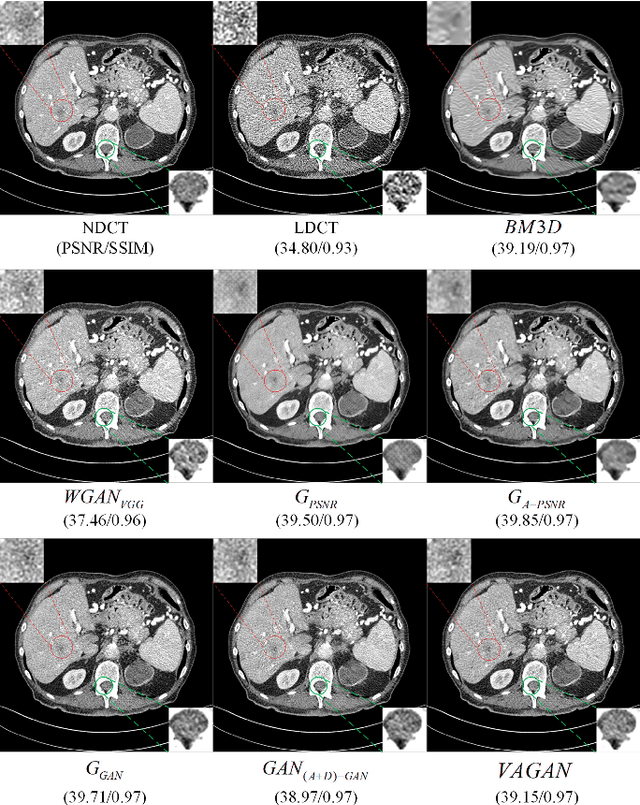

Abstract:Noise and artifacts are intrinsic to low dose CT (LDCT) data acquisition, and will significantly affect the imaging performance. Perfect noise removal and image restoration is intractable in the context of LDCT due to the statistical and technical uncertainties. In this paper, we apply the generative adversarial network (GAN) framework with a visual attention mechanism to deal with this problem in a data-driven/machine learning fashion. Our main idea is to inject visual attention knowledge into the learning process of GAN to provide a powerful prior of the noise distribution. By doing this, both the generator and discriminator networks are empowered with visual attention information so they will not only pay special attention to noisy regions and surrounding structures but also explicitly assess the local consistency of the recovered regions. Our experiments qualitatively and quantitatively demonstrate the effectiveness of the proposed method with clinic CT images.